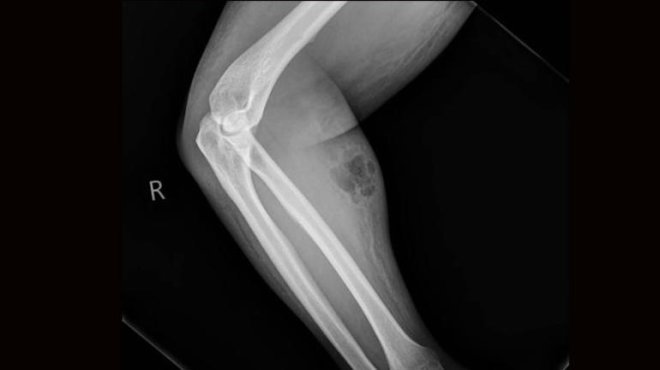

33 yaşındaki hasta, kronik sırt ağrısı şikayetiyle doktora başvurdu. Doktorlar, hastanın ön kolunda ciddi şekilde şişlik ve kızarıklık olduğunu fark etti.

Hastanın sırt ağrısını geçirme umuduyla, 18 ay boyunca koluna kendi spermini enjekte ettiği ve bu hareketinin ‘deri altı yangısı’ rahatsızlığına yol açtığı ortaya çıktı.